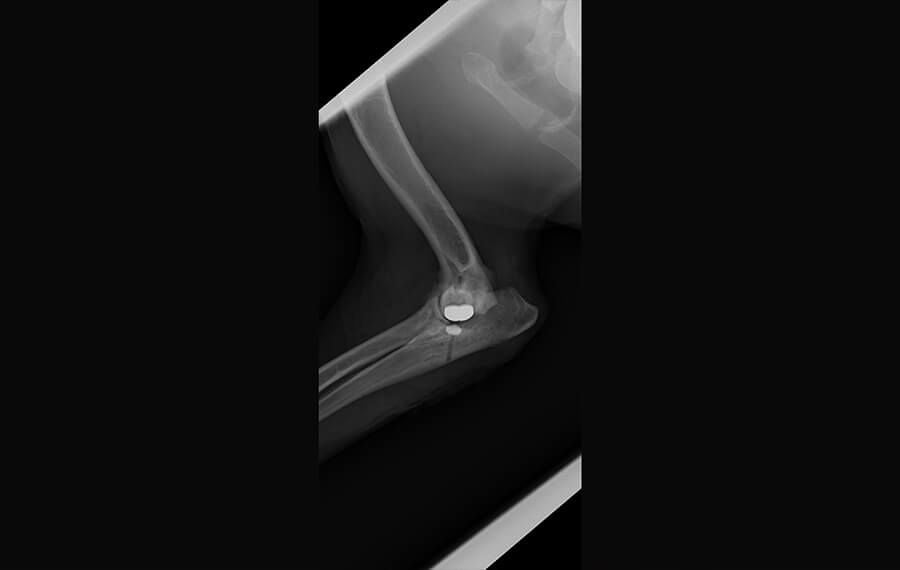

The Implants: We install a specialised metallic implant into the base of the humerus (thigh bone) and a high-strength synthetic "socket" into the ulna (shin bone).

The "Buffer" Effect: These implants meet in the middle to create a new, low-friction glide surface. This eliminates the painful grinding of raw bone against raw bone.